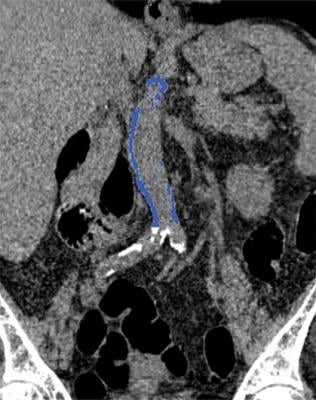

Abdominal Aortic Calcification May Signal Future Heart Attack